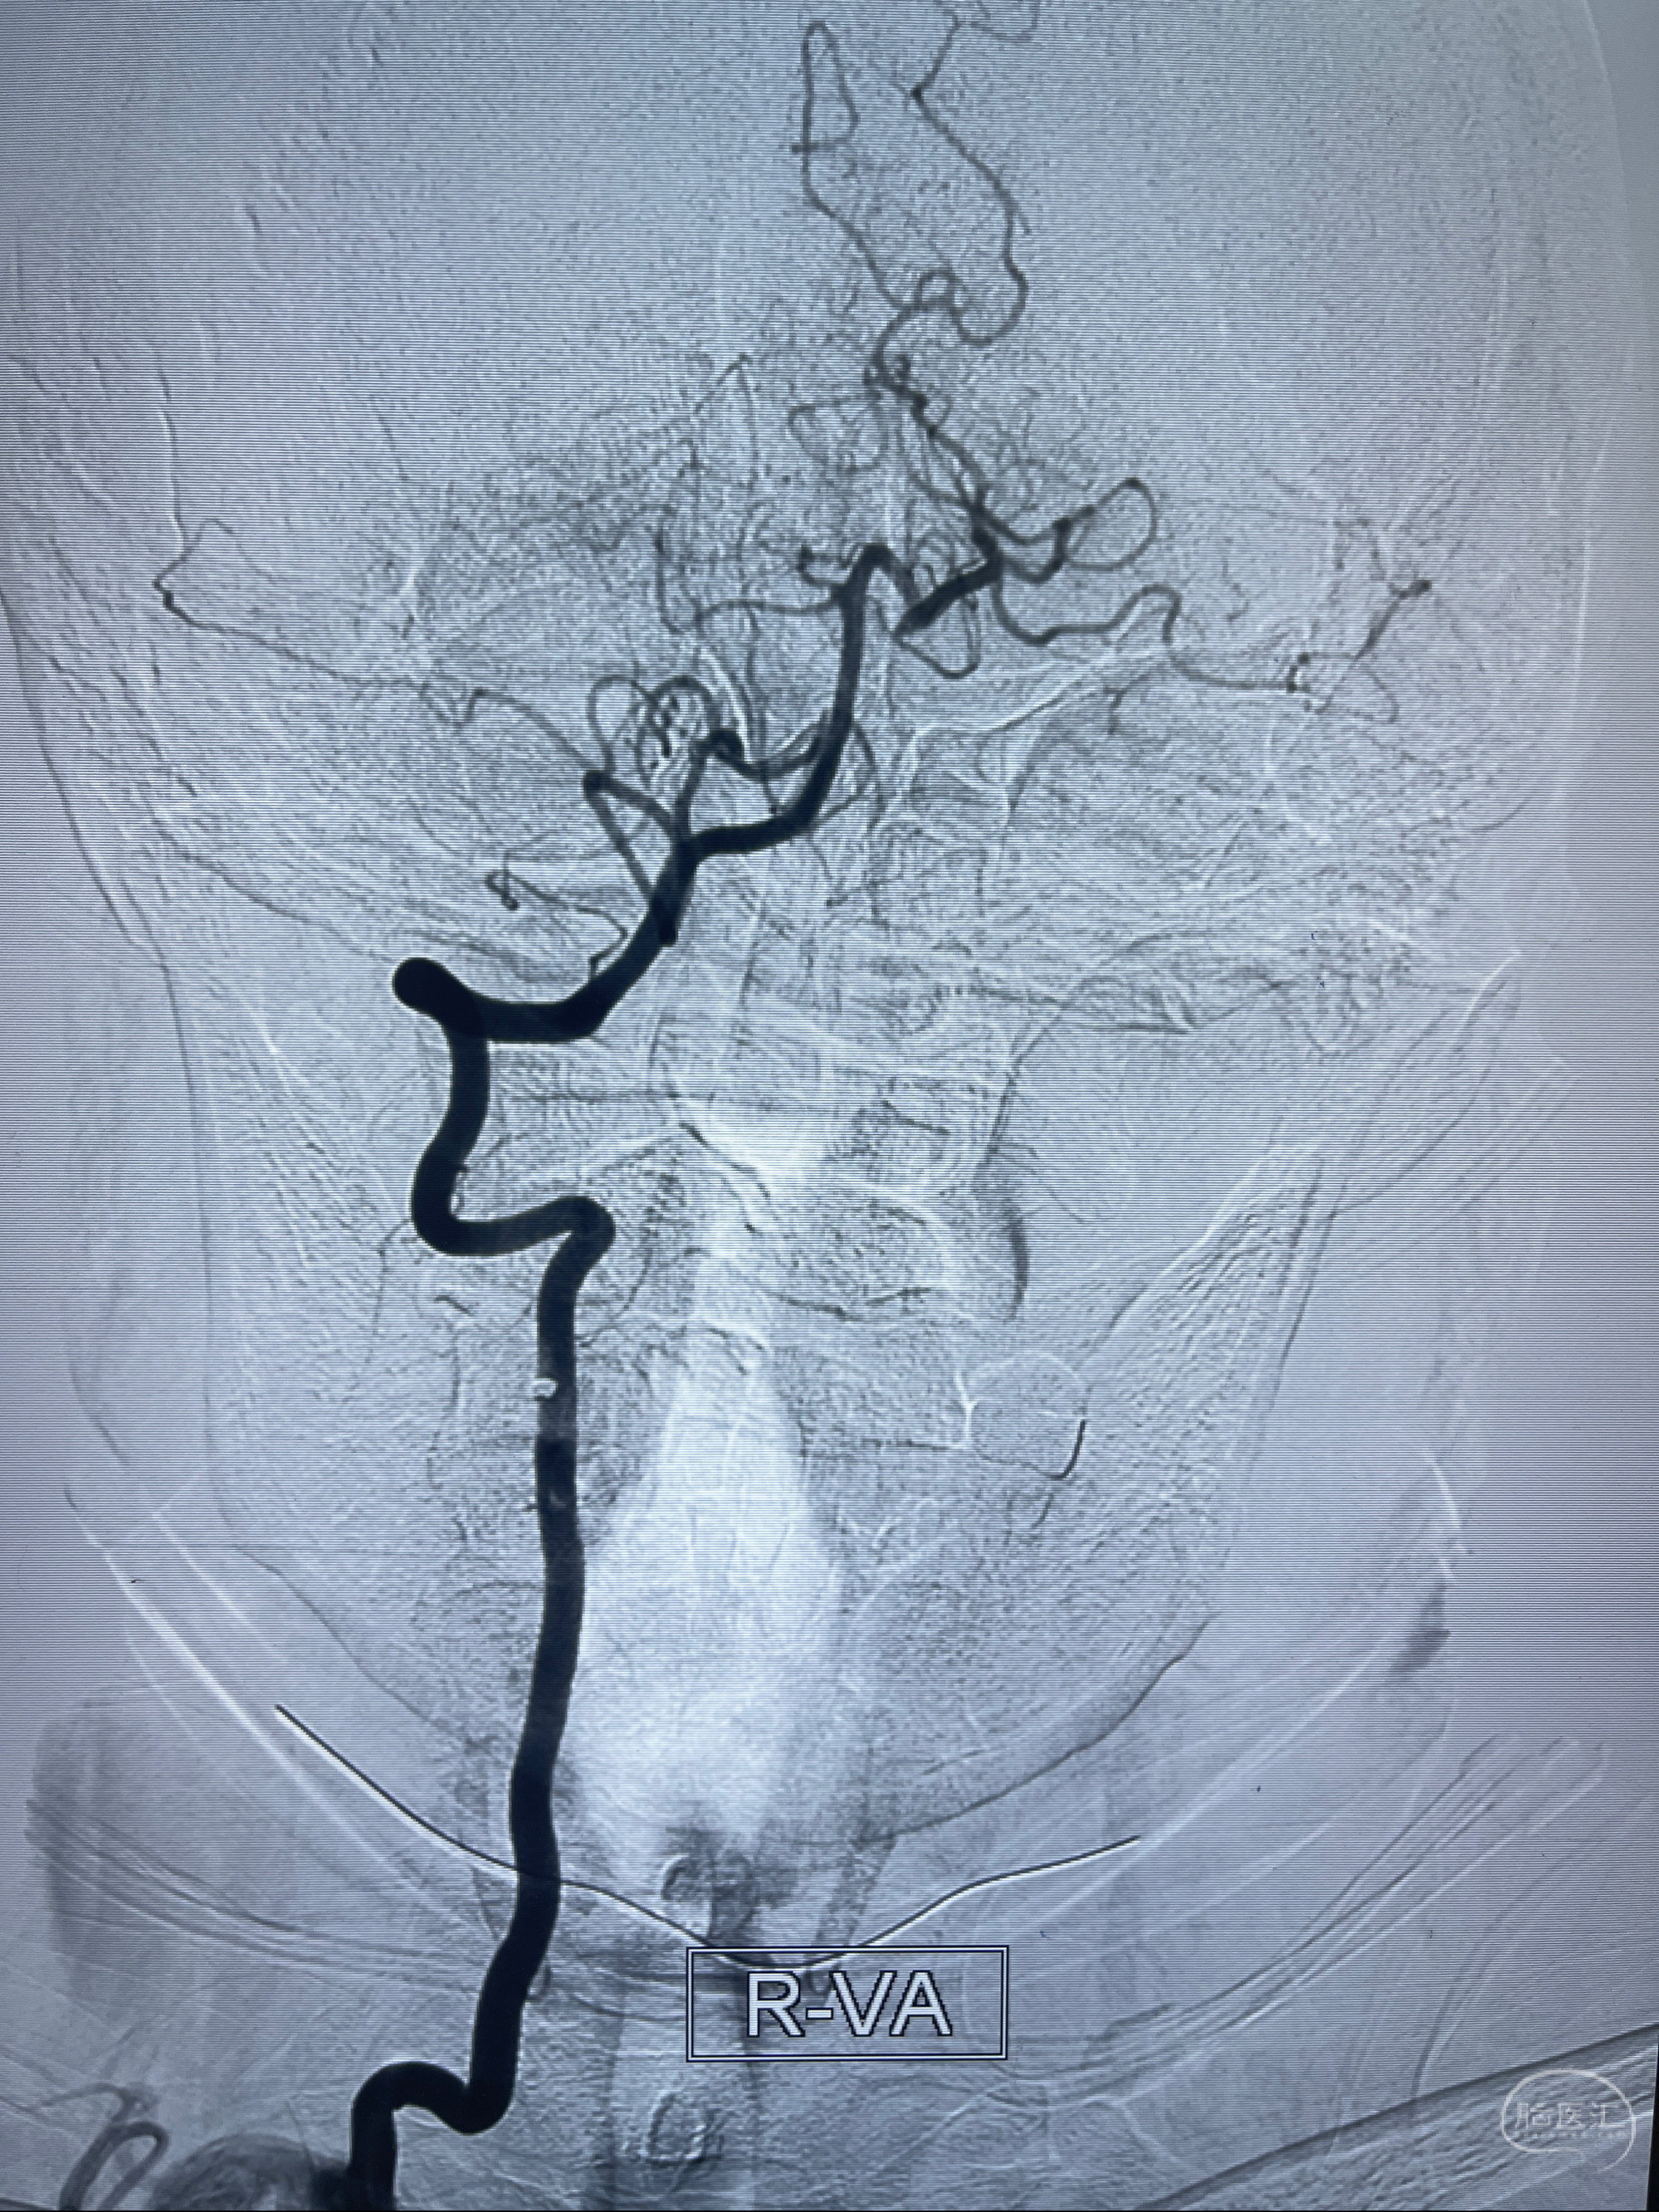

2023-02-02 沛县人民医院 头颅CTA:大脑动脉环发育变异,头颈部动脉粥样硬化,双侧颈内动脉及椎动脉颅内段多发狭窄;

1.双侧脑动脉狭窄

2.腔隙性脑梗死

2023-02-15DSA